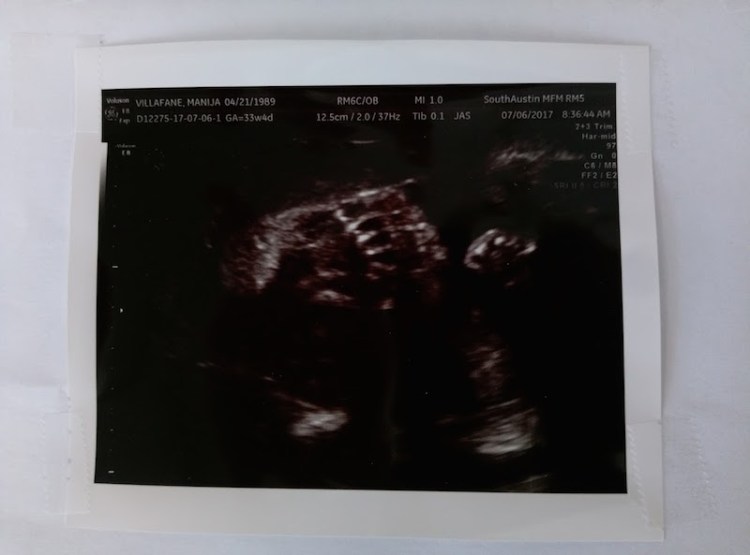

Went to the ultrasound at Advanced Fetal Medicine that my OB referred me to based on a concern of her femur length (too small), which never really worried us. The doctor at that place talked to us after analyzing the new ultrasound and he said that he looked at every aspect of the baby to look for any physiological abnormalities or deformities based on the short femur length and found absolutely none. I couldn’t tell them: “see this mom-to-be here? She’s tiny and was born uber-tiny also.”

This is the fourth ultrasound we’ve had and it seems that baby girl is always hiding with her hands, feet or both in front of her face. This time she had both a hand and a foot covering half of her face. The technician thought this was funny and called her “crazy baby.” I think she really meant to say: “weird baby”. And I’ll take it as a good thing. She also called her stubborn at one point. Something I’ve been called most of my life.

On this latest ultrasound, she also saw hair on her head already! Which I expected also based on her genes.